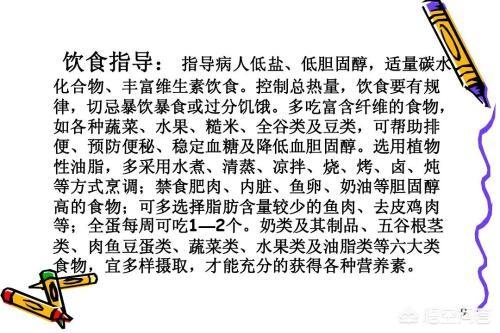

C'est pourquoi il est important de renforcer la publicité et l'éducation pour sensibiliser la population générale, en particulier dans les zones rurales, à la prévention précoce des accidents vasculaires cérébraux, afin qu'elle puisse mieux contrôler sa tension artérielle et sa glycémie, arrêter de fumer, limiter sa consommation d'alcool, suivre un régime alimentaire raisonnable et faire de l'exercice modéré, pour éviter ou réduire la survenue d'un accident vasculaire cérébral.

La prévention primaire de l'AVC consiste à contrôler strictement la tension artérielle et la glycémie sous la supervision d'un médecin, à réduire le poids, à arrêter de fumer, à limiter la consommation d'alcool, à faire suffisamment d'exercice physique, à maintenir de bonnes habitudes de vie et à se concentrer sur l'examen physique pour la détection précoce des facteurs de risque de l'AVC.

- Adoptez un régime alimentaire équilibré comprenant beaucoup de légumes et de fruits, et réduisez la consommation d'aliments riches en matières grasses.

- La tension artérielle, la glycémie et les lipides sanguins doivent être activement contrôlés en général pour éviter les maladies cardiovasculaires. Il est important de maintenir une tension artérielle stable, car une tension trop élevée ou trop basse peut provoquer un accident vasculaire cérébral.

- Évitez l'alcool et le tabac et maintenez une bonne hygiène de vie.

- Prenez l'habitude de faire régulièrement de l'exercice pour contrôler votre poids et éviter l'obésité.

- L'air froid a tendance à provoquer une vasoconstriction et une augmentation de la tension artérielle. Il convient donc de garder son corps au chaud lorsque le temps change radicalement.

- Les patients souffrant de maladies cardiaques telles que l'hypertension, le diabète, l'infarctus du myocarde, la myocardite, etc., doivent accorder une attention particulière aux signes d'alerte corporels, au diagnostic précoce et au traitement précoce en général.

- Supplémentation modérée en vitamine B6, vitamine B12, acide folique et autres nutriments pour réduire la concentration d'homocystéine dans le sang.